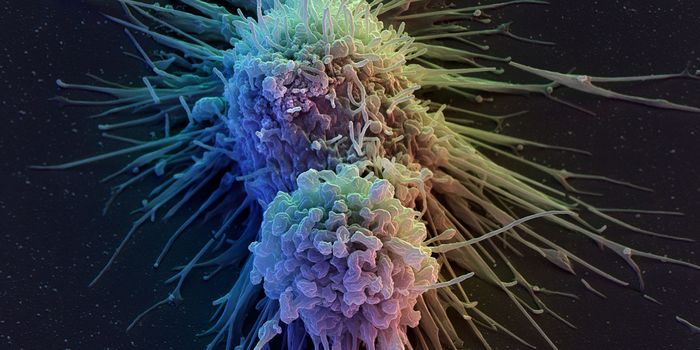

DEC 10, 2015ImmunologySuperior technology brings us novel images of cancer cells and lymphocytes this week, and now scientists can learn more ...